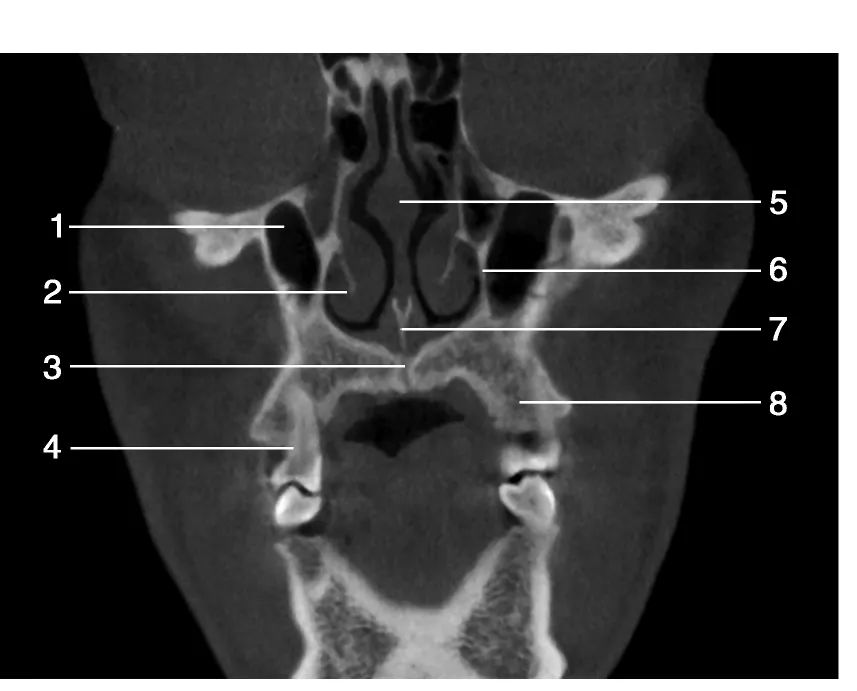

1.右侧上颌窦( right maxillary sinus) ; 2.下鼻甲( inferior turbinate) ; 3.腭中缝( median palatine suture) ; 4.上颌第二前磨牙( maxillary second premolar) ; 5.鼻中隔( nasal septum) ; 6.上颌窦内壁( inner wall of maxillary sinus) ; 7.犁骨( vomer) ;8.上颌牙槽骨( maxillary alveolar bone)